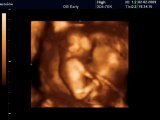

Wed 3000 Ultrason Görüntüsü - Hasvet Medikal

19 Haftalık Bebek Ultrason Görüntüsü

11 Haftalık Gebelik Bebek Ultrason Görüntüsü